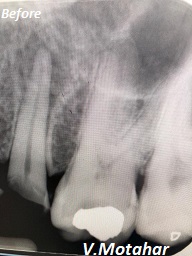

Root Canal Treatment on a molar teeth which had deep decay!

before

after